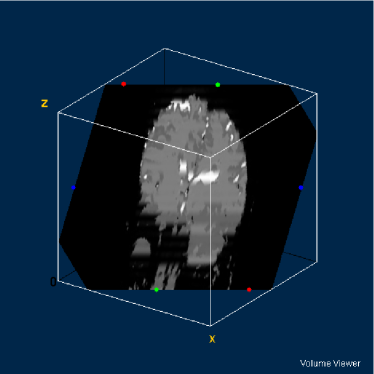

Figure 4: DW-MR volume with diffusion exponent of 0 s/mm2

Refer to caption

Figure 5: DW-MR volume with diffusion exponent of 500 s/mm2

Figure 6: DW-MR volume with diffusion exponent of 1000 s/mm2

The images can be considered as mathematical functions, where their domain is a region of the plain of the integers, called grid, and their counterdomain is the set of the possible values occupied by the pixels corresponding to each position of the grid.

Let fi:SW:subscript𝑓𝑖𝑆𝑊f_{i}:S\rightarrow W be the set of the diffusion-weighted MR images, where 1i31𝑖31\leq i\leq 3, SZ2𝑆superscriptZ2S\subseteq\textbf{Z}^{2} is the grid of the image fisubscript𝑓𝑖f_{i}, where WR𝑊RW\subseteq\textbf{R} is its counterdomain. The synthetic multispectral image f:SW3:𝑓𝑆superscript𝑊3f:S\rightarrow W^{3} corresponding to a determined slice of the volume composed by the DW-MR volumes presented in figures 4, 5 and 4 is given by: